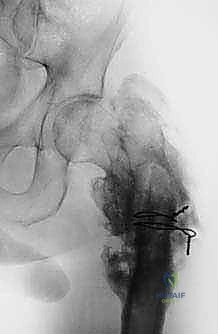

| الأشعة السينية (X-rays) | التقييم الأولي السريع لشكل العظم، اكتشاف الكسور المرضية، وتحديد نمط تدمير العظم. | تعطي الجراح فكرة عامة عن حجم المشكلة وموقعها. |

2. الأورام النقيلية (Metastatic Bone Disease)

عندما ينتشر السرطان من عضو آخر (مثل الثدي، الرئة، البروستاتا، أو الكلى) إلى العظام، فإن عظم الفخذ هو أحد أكثر المواقع عرضة لذلك بسبب حجمه وامتداد الأوعية الدموية فيه.

تؤدي هذه الأورام إلى تآكل العظم، مما يسبب ألماً مبرحاً ويجعله عرضة لما يسمى "الكسر المرضي" (انكسار العظم نتيجة إجهاد بسيط جداً بسبب هشاشته الشديدة). في هذه الحالات، يتم استئصال الجزء المدمر واستبداله بطرف اصطناعي لتخفيف الألم فوراً والسماح للمريض بالمشي مجدداً.